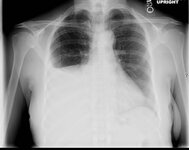

Pulmonary tuberculosis

Opacities in right lower lobe in a patient with pulmonary TB and diabetes

From the personal collection of David Horne and Masahiro Narita; used with permission